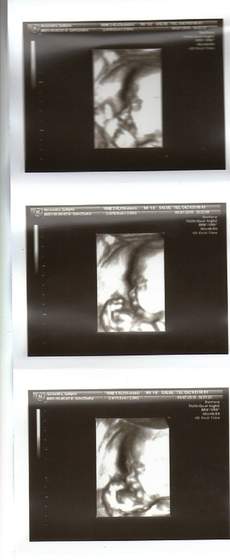

Ja w końcu pokarzę coś nowszego niż kropka :-D Zdjątka z połówkowego w 21tc (jakość kiepska bo robione aparatem z filmu na dvd)

2d:

No i 4d: